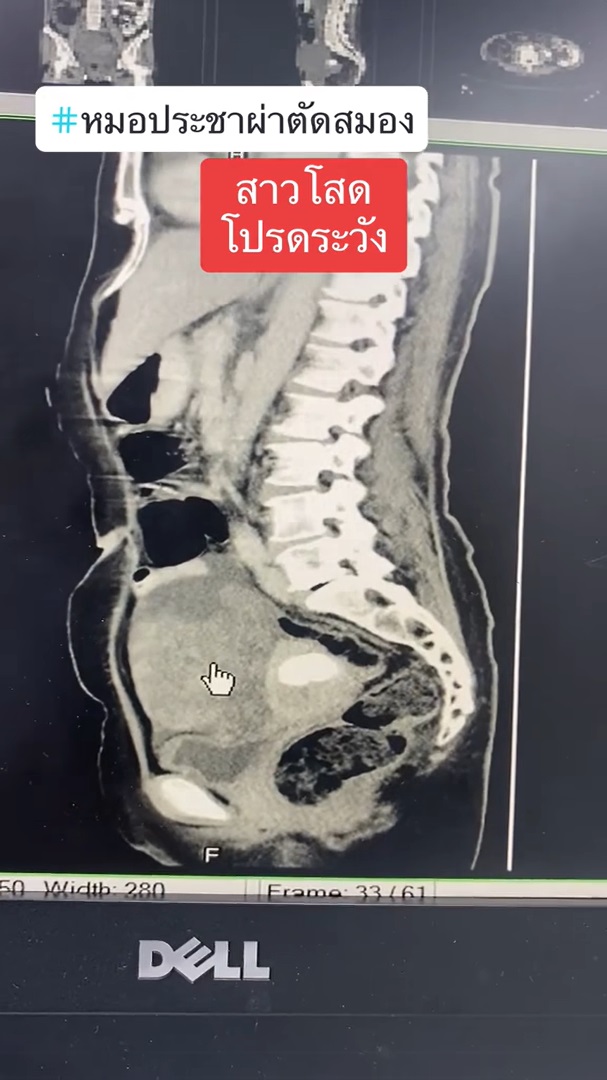

ทำเอาเหล่าสาวโสดถึงกับร้อน ๆ หนาว ๆ หลังจากที่ นายแพทย์ประชา กัญญาประสิทธิ์ หมอผ่าตัดสมอง ออกมาโพสต์เตือนภัยใกล้ตัวที่มีแนวโน้มจะเกิดกับสาวโสดได้ง่ายกว่าคนที่มีลูก โดยได้ยกเคสผ่าตัดเคสหนึ่งมาเป็นกรณีศึกษา ระบุว่า มีผู้ป่วยหญิง อายุ 57 ปี เป็นสาวโสดอยู่คนเดียว มาหาหมอด้วยอาการพูดจาสับสน ซึ่งผลการตรวจเอกซเรย์ พบว่า มีสมองตายหลายจุด ตายทั้งข้างหน้า ข้างหลัง ลามไปจนถึงท้ายทอย ทำให้ตามัว และมีจุดเลือดออกในหย่อมที่สมองตายด้วย และยังตรวจพบอีกหลายอย่าง อาทิ

โดยเคสนี้มาตรวจเนื่องจากญาติร้อนใจ หาสาเหตุไม่ได้ว่าทำไมสมองตายมากขนาดนี้ ก่อนจะเจอแจ็กพอตว่ามีก้อนเลือดเบ้อเริ่มอยู่ในอุ้งเชิงกราน ซึ่งอายุ 57 ปี ไม่ใช่การตั้งครรภ์อย่างแน่นอน พอเอาชิ้นเนื้อไปตรวจพบว่าเป็นมะเร็งรังไข่แล้วทำให้เกิดภาวะลิ่มเลือดไปอุดเส้นเลือดที่อวัยวะต่าง ๆ ของร่างกาย

แคลเซียมก็สูงมาก จากลักษณะของมะเร็ง ไม่ใช่กระจายไปที่สมอง ลิ่มเลือดอุดตันที่ขาสองข้าง ทำให้ขาบวม ทั้งยังเกิดลิ่มเลือดอุดตันในสมองหลายตำแหน่ง คนไข้จึงมาด้วยอาการพูดจาสับสน สุดท้ายกลายเป็นมะเร็งรังไข่ ซึ่งเคสนี้ก็ต้องผ่าตัดและสู้กับมะเร็งรังไข่กันต่อไป